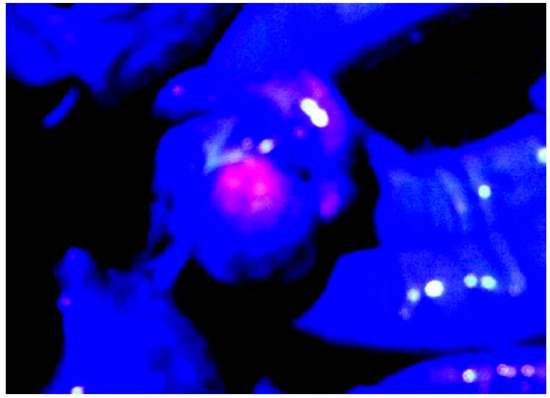

3.2. ALA PDD in Experimental PM

- Hino, H.; Murayama, Y.; Nakanishi, M.; Inoue, K.; Nakajima, M.; Otsuji, E. 5-aminolevulinic acid-mediated photodynamic therapy using light-emitting diodes of different wavelength in a mouse model of peritoneally disseminated gastric cancer. J. Surg. Res. 2013, 285, 119–126. [Google Scholar] [CrossRef]

- Canis, M.; Botchorishvili, R.; Berreni, N.; Manhes, H.; Wattiez, A.; Mage, G.; Pouly, J.L.; Bruhat, M.A. 5-amininolevulinic acid-induced (ALA) fluorescence for the laparoscopic diagnosis of peritoneal metastasis. An experimental study. Sur. Endoscopy. 2001, 15, 1184–1186. [Google Scholar] [CrossRef] [PubMed]

- Gahlen, J.; Pietschmann, M.; Prosst, R.L.; Herfarth, C. Systemic vs local administration of delta-aminolevulinic acid for laparoscopic fluorescence diagnosis of malignant intra-abdominal tumors-Experimental study. Surg. Endoscopy. 2001, 15, 196–199. [Google Scholar] [CrossRef]

- Hornung, R.; Major, A.L.; McHale, M.; Liaw, L.H.; Sabiniano, L.A.; Tromberg, B.J.; Berns, M.W.; Tadir, Y. In vivo detection of metastatic ovarian cancer by means of 5-aminolevulinic acid-Induced fluorescence in a rat model. J. Am. Assoc. Gynecol. Laparoscopist. 1998, 5, 141–148. [Google Scholar] [CrossRef]

- Lüdicke, F.; Gabrecht, T.; Lange, N.; Wagnières, G.; van Den Bergh, H.; Berclaz, L.; Major, A.L. Photodynamic diagnosis of ovarian cancer using hexaminolevulinate: A preclinical study. Br. J. Cancer. 2003, 88, 1780–1784. [Google Scholar] [CrossRef] [PubMed][Green Version]